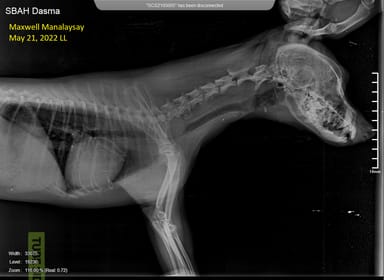

Is my dog's x-ray showing collapsed trachea or just a fuzzy image?

Hello Docs, I just wanted to ask if this x-ray of my dog indicates a collapsed trachea or is the section where it seems collapsed just fuzzy in the image. Thank you

Hi and thanks for your request The trachea does not seem collapsed but there may be a radiopacity superimposed on top of the trachea at the level of thoracic inlet. This may be on the left or right side, pushing the trachea sideway. A ventro-dorsal view or an ultrasound should be performed to assess this.